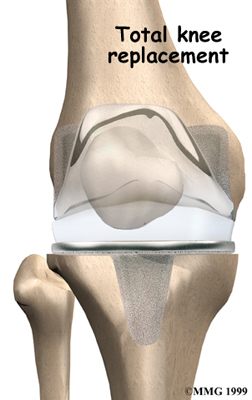

Artificial Knee Replacement

An artificial knee replacement is the ultimate solution for advanced knee OA.

Surgeons prefer not to put a new knee joint in patients younger than 60. This is because younger patients are generally more active and might put too much stress on the joint, causing it to loosen or even crack. A revision surgery to replace a damaged prosthesis is harder to do, has more possible complications, and is usually less successful than a first-time joint replacement surgery.

Related Document: FYZICAL West Ashley's Guide to Artificial Joint Replacement of the Knee